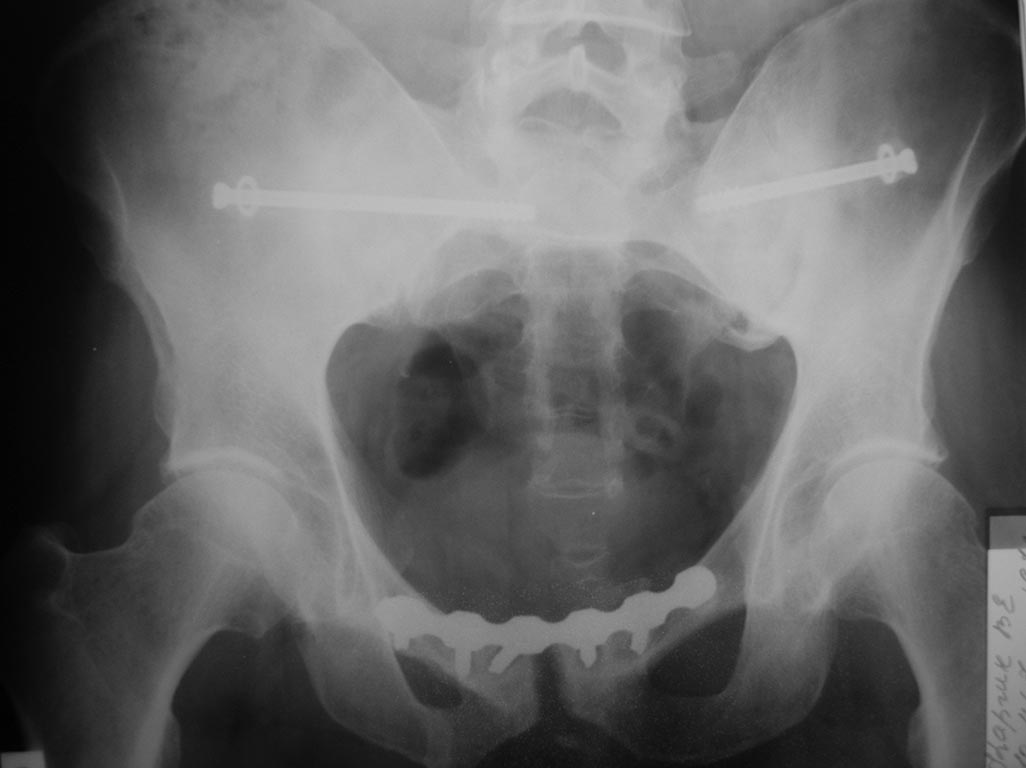

Пациент 43 лет. Травма в ноябре прошлого года. Оперирован у нас в отделении. Послеоперационный период гладкий. В настоящий момент пациента ничего не беспокоит, вернулся к прежней тяжелой работе (промывальщик цистерн). Категорически настаивает на удалении металла. Проблема в том, что оперируем таз мы достаточно часто, а вот удалять не приходилось. Вопрос: стоит удалять, и если стоит, то не рано ли? Спасибо всем откликнувшимся.